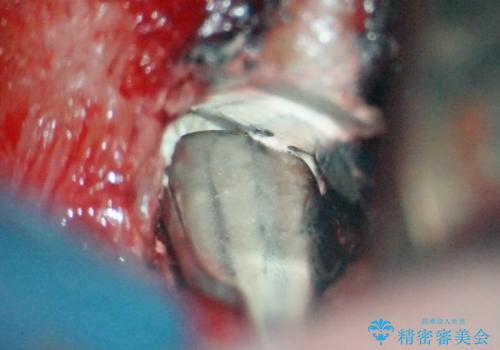

前医にてラバーダムを用いた根管治療が完了していたため、歯根の先端を切除する治療を行いました。

手術をした後は、7日ほど痛みと腫れが出ます。